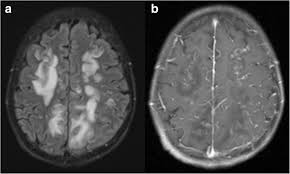

Neuromuscular Manifestations of Sjogrens syndrome Patients suffering from Sjogrens syndrome may develop a whole variety of neuromuscular complications. Additionally hyperintense T2 lesions on brain MRI may be present and can appear similar to lesions seen in multiple sclerosis. In addition Sjogrens syndrome may cause skin nose and vaginal dryness and may affect other organs of the body including the kidneys blood vessels lungs liver pancreas and brain.

Dr Balaji Anvekar Frcr Sjogren S Syndrome Mri Brain

Neuromuscular Manifestations of Sjogrens syndrome Patients suffering from Sjogrens syndrome may develop a whole variety of neuromuscular complications. The first is ichthyosis which is a buildup of skin to form a scale-like covering that causes dry skin and other problems. Primary Sjogrens symptoms and objective signs of ocular dryness with positive Schirmers test and positive Rose-Bengal or fluorescein staining of cornea and conjunctiva. Primary Sjogrens Syndrome symptoms are pure sensory neuropathy sensorimotor neuropathy neuronopathy cranial nerve involvement polyneuropathy mononeuritis multiplex and polyradiculoneuropathy. Additionally hyperintense T2 lesions on brain MRI may be present and can appear similar to lesions seen in multiple sclerosis. Sjögrens syndrome SS is a chronic autoimmune inflammatory disorder characterized by diminished lacrimal and salivary gland function. Sjögrens syndrome can cause a numbness or burning of the face called trigeminal neuralgia Pain in the back of the throat which may worsen while swallowing is called glossopharyngeal neuralgia Patients with trigeminal or glossopharyngeal neuralgia can have agonizing mouth and facial pain. Neurologic involvement occurs in approximately 20 of patients with primary Sjögren syndrome SS. Symptoms often vary from patient to patient including in severity While many patients experience dry eyes dry mouth fatigue and joint pain Sjögrens can also cause dysfunction of organs such as the kidneys gastrointestinal system blood vessels lungs liver pancreas and the central nervous system.